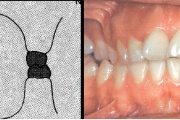

Sügav hambumus

Normaalse jäävhammaskonna pilt küljelt ja eest vaadatuna.